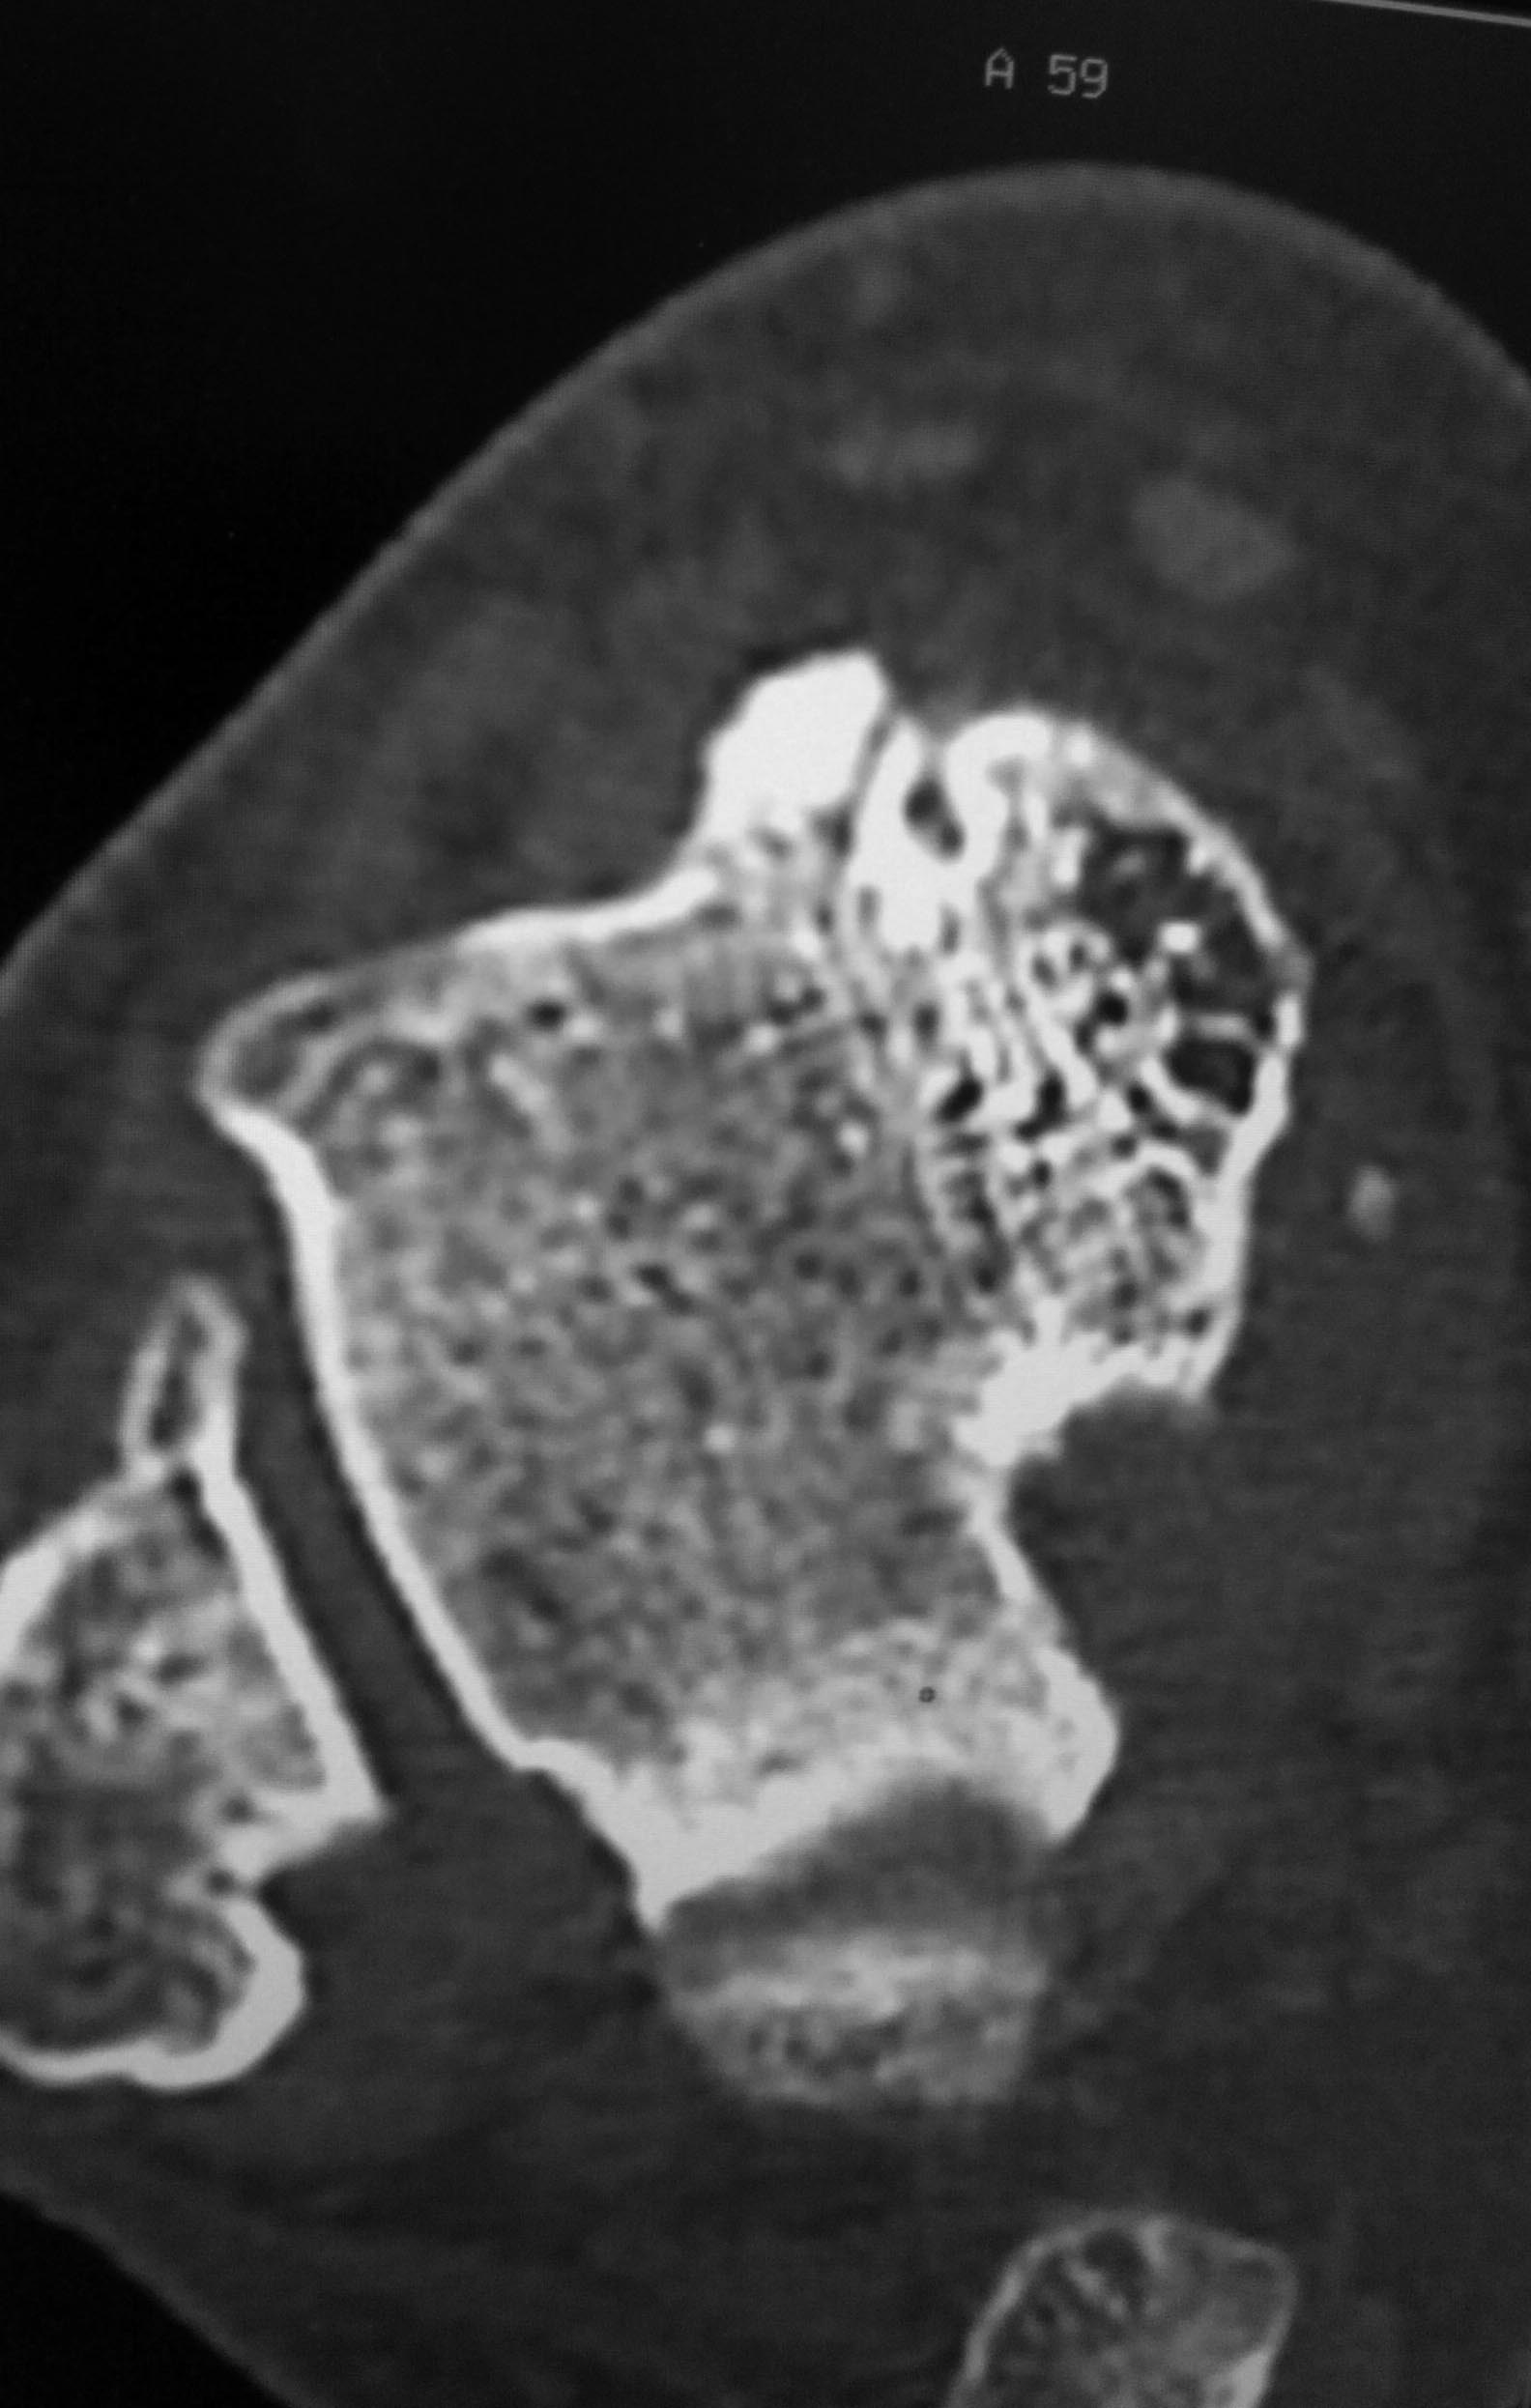

Я бы еще повниматьнее к таранной кости присмотрелся. Не было ли перелома ее шейки? На КТ срез подозрительный, но только один.

Я тоже согласен, на одном из КТ-снимков, подозрение на перелом шейки таранной кости.

Также есть подозрение на перелом таранной кости по КТ.

Вколоченный перелом шейки таранной шейки кости,переднего края Б/берцовой кости.МОС шейки таранной кости,удаление костно-хрящевых экзостозов.